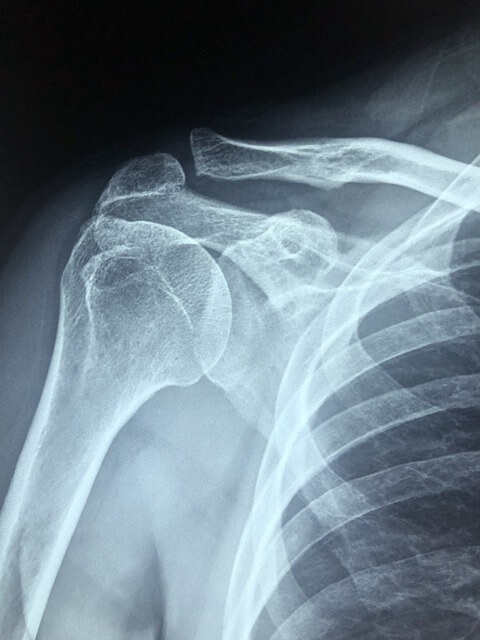

어깨 통증은 현대인들이 흔히 겪는 문제 중 하나로, 잘못된 자세나 스트레스, 장시간 컴퓨터 작업 등 다양한 원인에 의해 발생할 수 있습니다. 이로 인해 일상생활에 불편을 느끼는 경우가 많습니다.